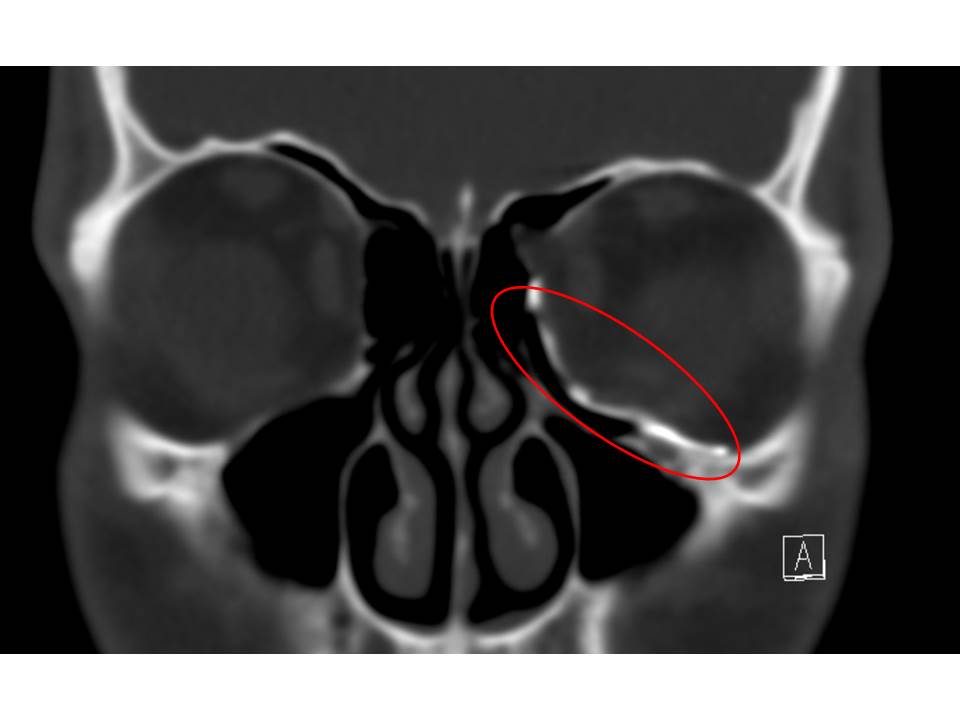

After a CT scan the healthy orbit is mirrored to the fractured one. The mirrored orbital floor is used as guide for a custom made craniofacial implant. The implant is designed on the computer and then 3D printed in titanium. The implant is inserted to the orbital floor and fixed with screws to the lower orbital rim (Figure 9).

Figure 9: A custom-made titanium implant inserted to reconstruct the fractured orbital floor. The implant is retained with screws in the lower orbital rim.

The aim is to nearly normalise the orbital volume and remove adhesions to the fracture which can cause double vision by impacting the optic nerve. Clinical evaluation of eye movement and vision is used to assess the outcome and a CT scan is performed to assess the fit of the implant (Figure 10).

Figure 10: A postoperative CT scan illustrating the position of the custom-made craniofacial implant. The red circle marks the implant.